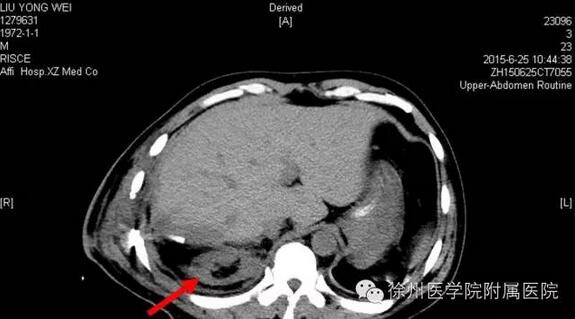

该声明称,患者手术时间是2015年6月20日,术后分别于2015年6月21日(术后第1天)和6月25日(术后第5天)的2次CT复查均显示该患者的右肾存在。

该声明还专门张贴了两张CT复查图。

图二2015年6月25日(术后第5天)CT,右肾如箭头所示。